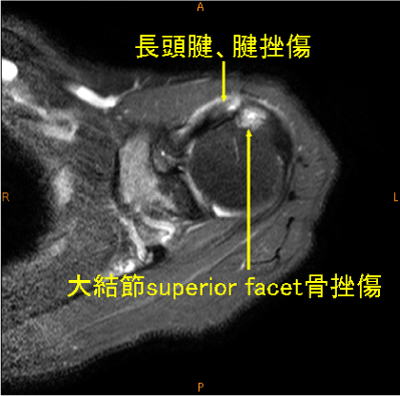

長頭腱の腱挫傷は稀な所見である。

脂肪抑制T2WIでないと描出が難しい。

大結節前方(superior facet)の骨変化は棘上筋腱の損傷を高頻度に合併している。

長頭腱腱挫傷, 大結節の骨挫傷, 棘上筋腱腱挫傷